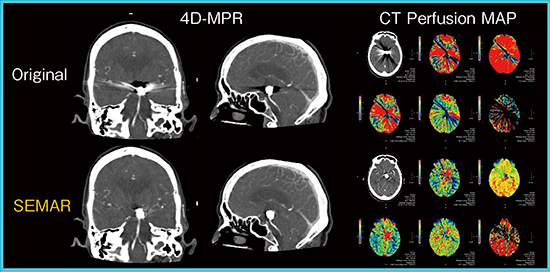

3.Single Energy Metal Artifact Reduction(SEMAR)

SEMARは,Single Energyデータに対し金属アーチファクトを低減する画像再構成技術で,Forward projection,Back projectionを複数回繰り返し行うことで,金属アーチファクト成分のみを効果的に除去する。CT Perfusionでは金属近傍の信号が欠けることで乱れたマッピングになることがあるが,SEMARをかけることで改善できる(図2)。当初,SEMARは再構成時間が長いことが課題だったが,高性能GPUの搭載やアルゴリズムの最適化などで,現在はヘリカルスキャンで約5.5倍,ボリュームスキャンで約2.3倍高速化されている。

図2 SEMARによるCT Perfusion画像